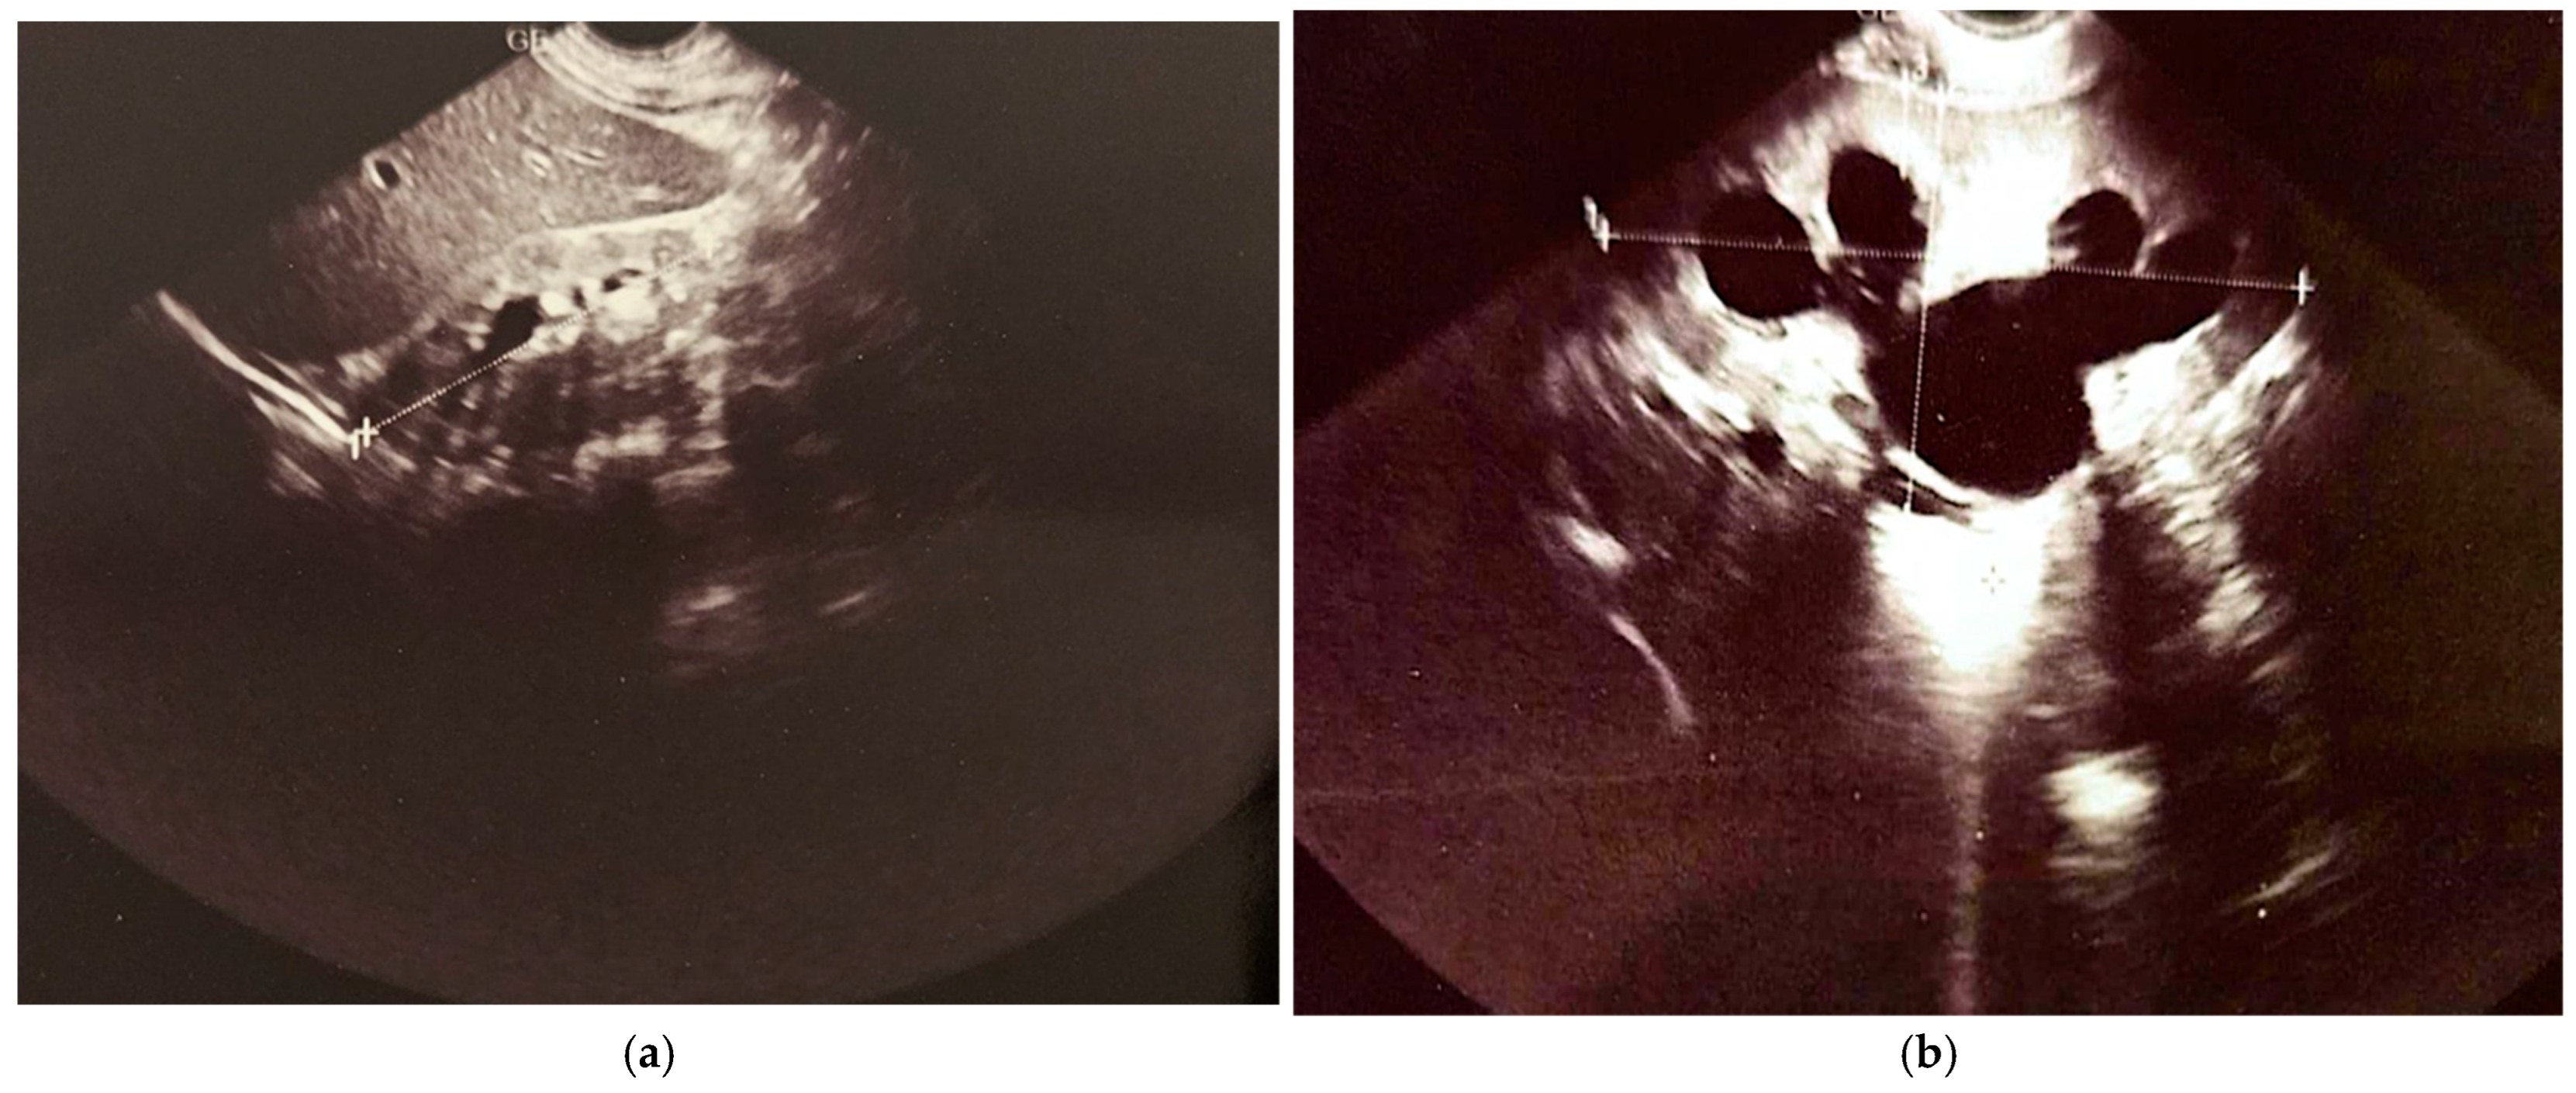

The last abdominal ultrasound performed at 7 years of life revealed that the right kidney, located in the renal fossa, appeared hypoplastic. It maintained a regular shape and contour and was mobile with respiration. Its dimensions were 6.7 × 2.4 cm, with a parenchymal index (PI) of 9 mm. The pyelocaliceal system of the right kidney showed mild distension in the upper calyceal group, and no calculi were present. In contrast, the left kidney, also situated in the renal fossa, displayed a regular shape and contour with good respiratory mobility. It measured 10.4 × 4.8 cm, with a PI of 11 mm at the upper pole. Notably, the pyelocaliceal system of the left kidney was dilated; the renal pelvis and calyceal groups measured approximately 3.3 × 3 cm, and no calculi were observed. The left ureter was clearly visible at the renal hilum, measuring approximately 11 mm in diameter. The urinary bladder contained anechoic fluid and exhibited thickened walls. The left ureter could be visualized in its lower third, measuring about 8 mm in diameter, while the right ureter was seen at its entry into the bladder. The initial conclusions drawn from this ultrasound included grade III/IV hydronephrosis of the left kidney, a hypoplastic right kidney, and a status post complete repair of pyeloureteral duplication. The final conclusions further clarified that the right kidney demonstrated grade I hydronephrosis, the left kidney showed grade III/IV hydronephrosis, and there was evidence of a neurogenic bladder, all in the context of a previously completed repair of pyeloureteral duplication on the right side (Figure 8).

Figure 8.

Renal ultrasound: (a) hypoplastic right kidney; (b) pelvicalyceal dilation of the left kidney; (c) dilated renal pelvis and ureter on the left kidney; (d) bladder with a modified (“funnel-shaped”) appearance; (e) pelvic dilation of the left kidney; (f) ureter dilated at the hilum of the left kidney.